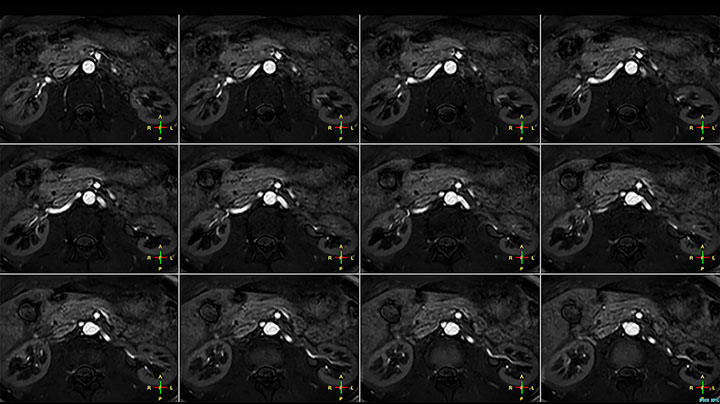

Although the area between the neck and the top of the lung is one of the most difficult areas for MRI, Prodiva 1.5T images show good quality in this 56-year-old male with Pancoast tumor on the right. mDIXON TFE images shows excellent fat suppression in the neck area and the DWI shows almost no distortion.